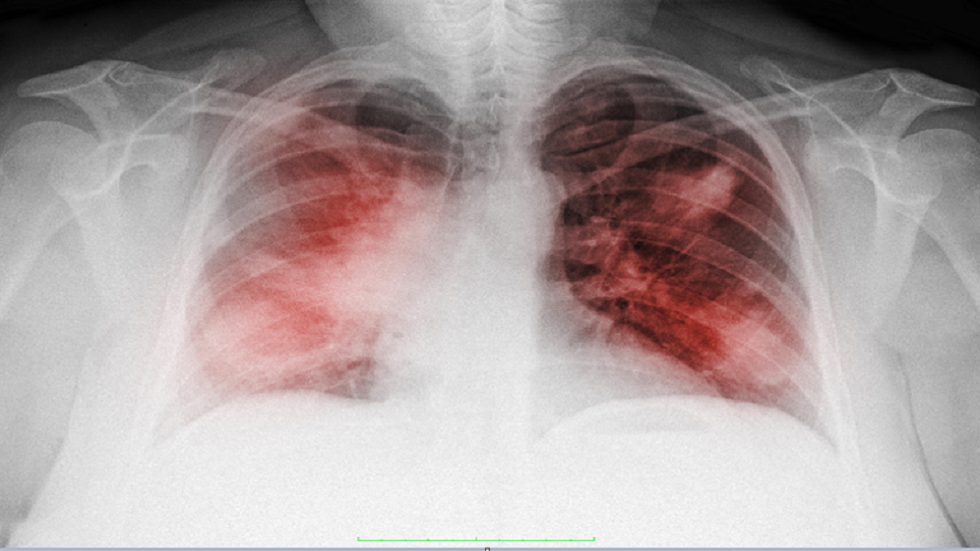

التهاب الرئة.. الأسباب وعوامل الخطر وطرق التشخيص

يشير الأطباء إلى أن التهاب الرئة هو التهاب في أنسجة الرئة يحدث غالبا كأحد مضاعفات العلاج المناعي، ويصاب به كثير من مرضى السرطان.

روسيا.. اكتشاف فيروس يقضي على مسببات الالتهاب الرئوي

ووفقا للأطباء، يحدث التهاب الرئة في 3-10٪ من الحالات كمضاعفات للعلاج المناعي، وتصل نسبة الوفيات إلى 35٪. ويعد هذا الالتهاب أثرا جانبيا لاستخدام مثبطات نقاط الضبط المناعية، كما يمكن أن تسببه عوامل مختلفة، بما في ذلك تأثير منظومة المناعة على خلايا الورم.

ويهدف العلاج المناعي باستخدام مثبطات PD-1 وPD-L1 إلى تثبيط الآليات التي تستخدمها خلايا الورم للدفاع عن نفسها ضد الجهاز المناعي. ومع ذلك، قد تؤدي هذه العملية إلى تفاعلات مناعية ذاتية، بما في ذلك التهاب الرئة، الذي يصيب الرئتين ويتطلب تدخلا طبيا في كثير من الحالات.

وتشمل عوامل الخطر الرئيسية للإصابة بالتهاب الرئة أمراض الرئة المزمنة، مثل أمراض الرئة الخلالية، والتدخين، واستخدام العلاج المناعي مع علاجات أخرى. كما أن بعض أنواع السرطان، وخاصة سرطان الخلايا الكلوية، ترتبط بزيادة احتمالية الإصابة بالتهاب الرئة مقارنة بأنواع الأورام الأخرى.

ويتم تشخيص هذا المرض عبر التصوير المقطعي المحوسب للكشف عن وجود تصلب في أنسجة الرئة، بالإضافة إلى تحليل غسل القصبات الهوائية الذي يساعد على استبعاد الأمراض المعدية. وفي حال تأكدت الإصابة بالتهاب الرئة، يصبح من الضروري تعديل العلاج لمنع تفاقم حالة المريض.